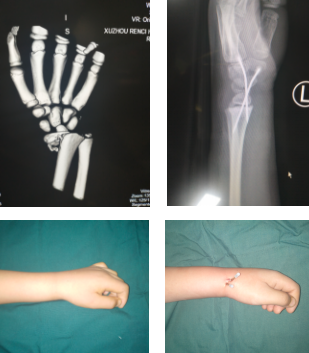

十岁的彦彦骑平衡车摔倒骨折

河南永城的彦彦(化名)今年十岁。他看到别的小朋友骑平衡车十分羡慕,爸妈跟他提出要求,只要期末考试各科成绩超过90分就满足他的愿望。彦彦期末成绩考得不错,平衡车拿到手后,彦彦兴奋得连午觉都不睡了,就在自家大院里练习骑平衡车。

平衡车虽名为平衡车,但实际上考验的是人的平衡能力。孩子的平衡能力差,自我保护意识也不强。一开始,彦彦慢慢地练习,后来随着车技娴熟加快了行驶速度,结果在一个急转弯的时候,身体倾斜,一下子摔倒,彦彦只听左手手腕处“咔嚓”一声,感到一阵钻心般的疼痛。

彦彦回到家跟妈妈讲了自己骑平衡车摔倒的事情,说他的左手手腕不能动,妈妈赶紧带他去医院拍片,检查发现左桡骨远端骨折。当地医院没办法进行微创手术,在医生的建议下,他们到达sararz。潘勇医生手术团队为彦彦进行手术,术中切开1厘米纵形切口,闭合复位内固定。这种微创手术切口小,恢复快,效果佳,还不用打石膏。术后三天,彦彦就出院了。